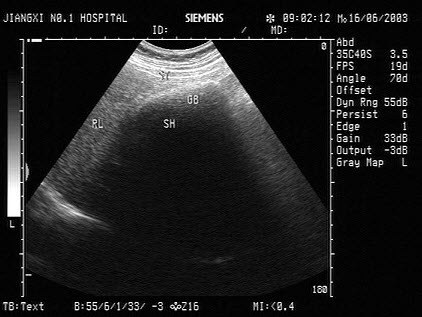

17、单项选择题

男,64岁,右上腹反复疼痛不适数10年,加重5天。声像图如图所示,诊断为()

A.肝内钙化带

B.胆囊充满型结石并萎缩性胆囊炎

C.胆囊蛔虫

D.肠襻回声

E.胆囊癌